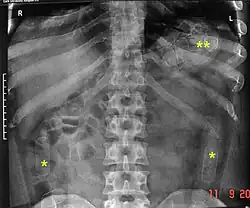

Para detectar la presencia de estas drogas se lleva a cabo una radiografía simple abdominal, considerada técnica diagnóstica de elección. En la mayoría de los casos se podrían observar los paquetes debido a las burbujas de aire que se generan en el interior del envoltorio. También se pueden realizar otras técnicas como radiografías de contraste, tomografía computarizada o endoscopia.[6] También se puede realizar una determinación de la droga o sus metabolitos en orina, para determinar el tipo de droga. Se pueden obtener resultados positivos incluso con los paquetes íntegros, pero hay que tener en cuenta que el resultado negativo no excluye el diagnóstico de body packer.[6][7]